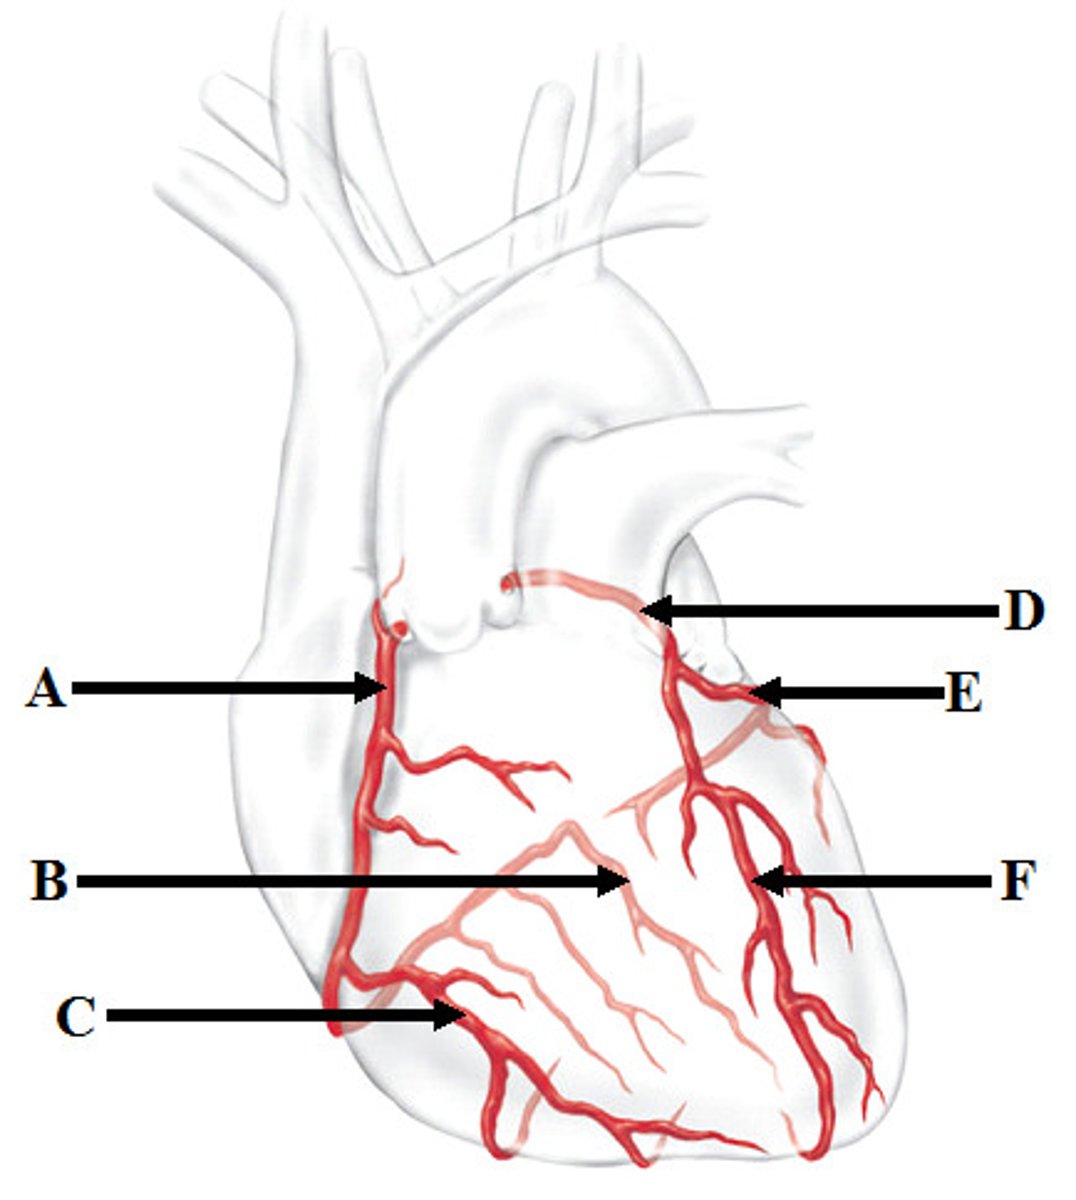

Coronary arteries (right (A) and left(D))

Marginal artery (C) and Posterior Interventricular artery (B)

Branches of right coronary artery

Anterior Interventricular artery (F) and Circumflex artery (E)

Branches of the left coronary artery